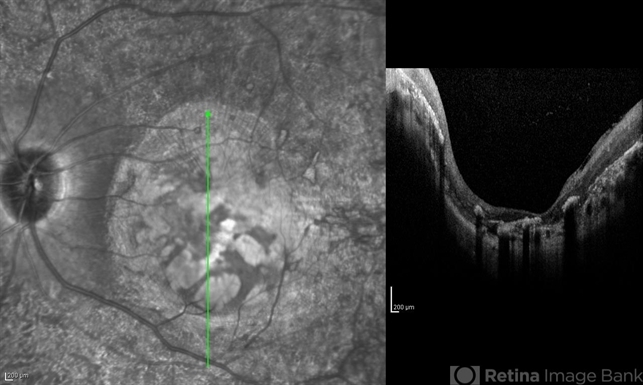

- infrared image

Optical coherence tomography system

Spectralis OCTc - Description

- Infrared and OCT images of the left eye of a 25-year-old woman with bilateral macular colobomata and pigmentary retinopathy similar to Leber's congenital amaurosis.